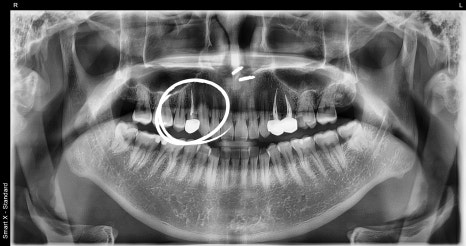

신경치료 및 크라운 치료완료 사진

신경을 빼면 치아는 “껍데기”만 남게 됩니다.

안쪽이 비어 있어서 예전보다 훨씬 약해집니다.

특히 어금니는 씹는 힘을 많이

받기 때문에 깨질 위험이 높습니다.

그래서

내부를 레진으로 튼튼하게 채워주고

바깥쪽에는 지르코니아 크라운으로

단단한 뚜껑을 씌워서 보호합니다.

이렇게 해야 신경치료한 치아를 오래 사용할 수 있습니다.